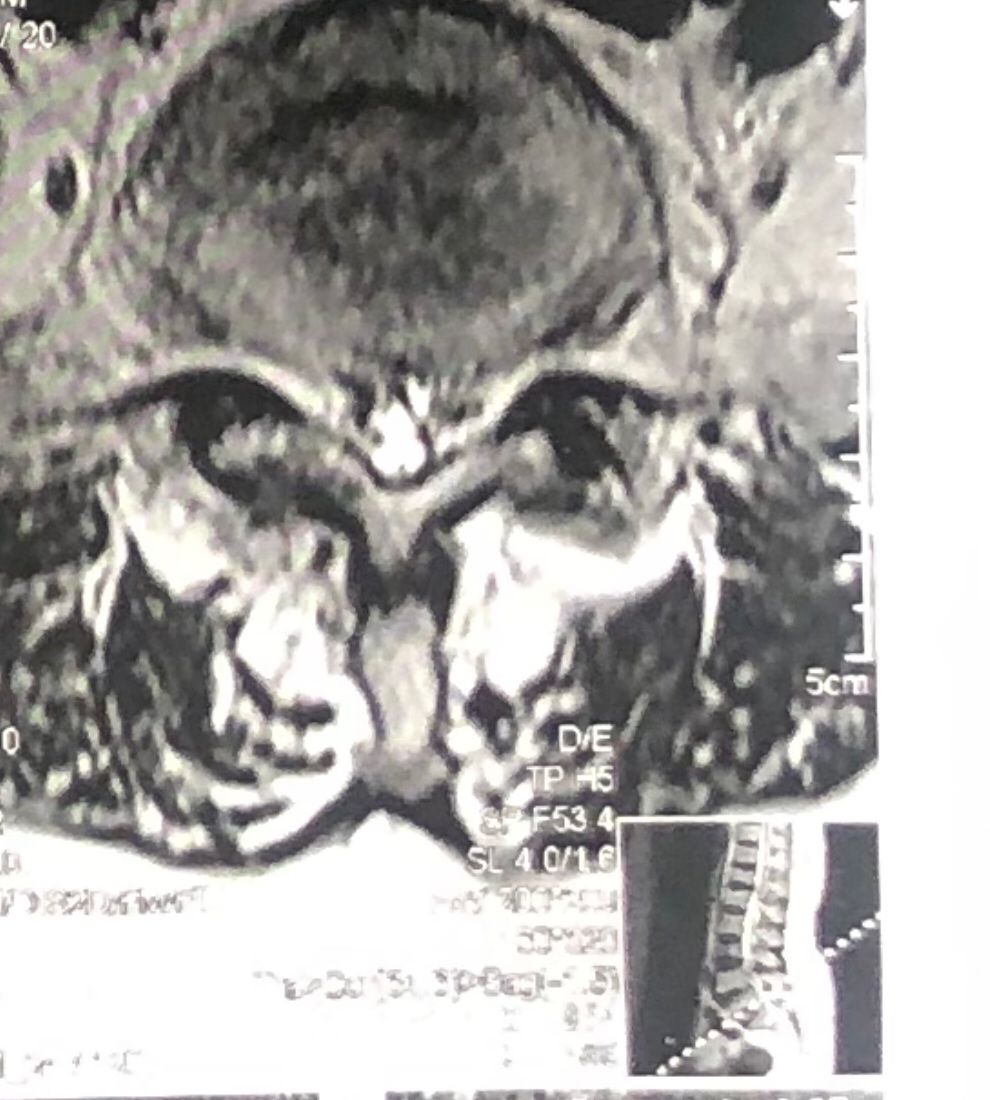

In his MRI was reported R. para R. IVF Massive extrusion. I decided to control his pain and manage this patient with reevaluation of patient every other session. For 5 sessions i just used acupuncture and laser and IFC and mild adjustments to his R. T3-T7 and mild arthosteem to above and below involved segment. Cervical adjustment considered contraindicated for this patient. From session 6th- 8th i started to use mild/gentle cervical decompression. He used soft cervical collar all the time. His pain decreased by 80 percent

I gave him cervical traction pump to be used 3-5 times per day at home for the next 3 months and i released the patient. He was evaluated every week once for one month and after that every 2 weeks. After 3 month I repeated MRI. Size of the herniated disc was reduced greater than 50 percent. Asked him to do another mri in 6 months

MRIs before and after proper management of this patient: